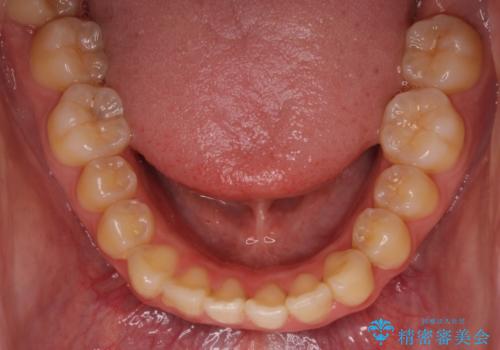

- 口元が出てるのが気になるとのことで来院されました。

歯のがたつきはあまりなかったのですが、口唇が閉じずらく、口元の突出感が確認できました。

上下左右の歯を1本ずつ抜歯して、そのスペースを利用して口元を引っ込める計画としました。